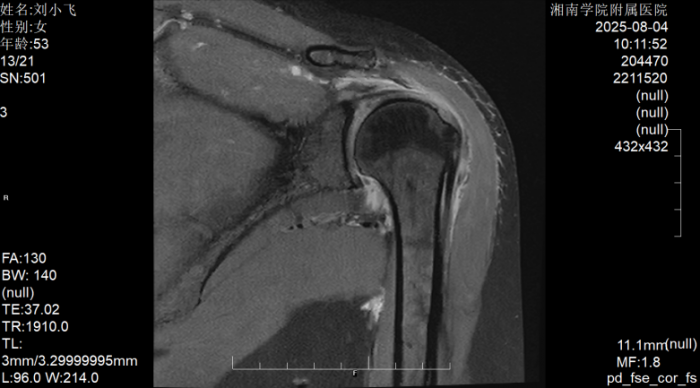

据了解,患者刘阿姨因左肩部疼痛辗转求医多日,尝试吃药、针灸、推拿等多种治疗后症状不仅未改善,反而持续加重,最终发展到无法端碗吃饭、自行穿衣洗澡的程度。转诊至江南娱乐网址登录 后,经术前MRI检查确诊为巨大肩袖撕裂,且肩袖缺损范围大、肌腱质量差,传统修复方式难以达到理想效果。